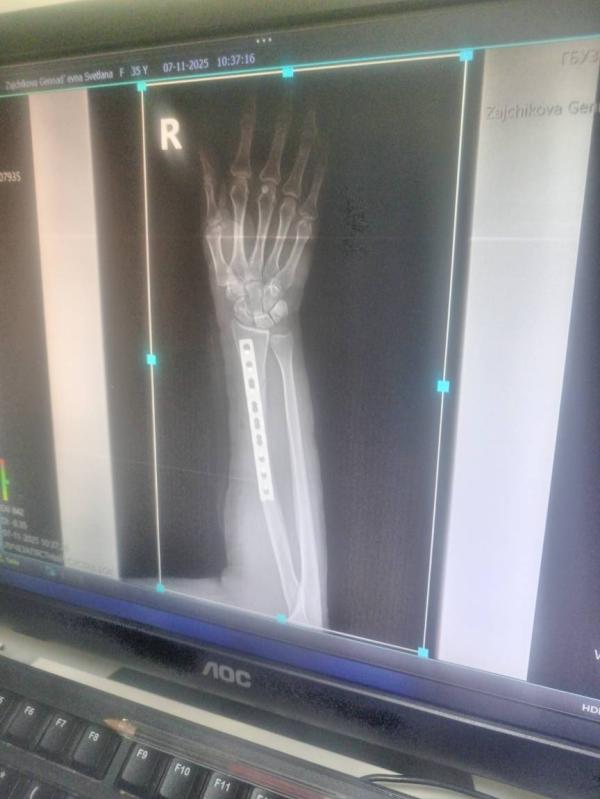

Девочки, кто сталкивался с подобным, перелом с отломками, операция. Делали в зипе, врачи в двух словах хамло и быдло, отношение скотское, таких только на ферму свиней рубить, а не людей чинить. Никакой информации не выпытать, все вопросы сливаютс или пкрекидывают спросить у другого врача, лечащий/дежурный, никого в кабинете вечно нет. Принесла медсестра выписку. Мои вопросы без ответов. Самый волнующий, я не чувствую большой палец и внешнюю сторону ладони, это норма? Или косяк Анастезиолога?

Это началось после операции, вся рука постепенно отошла от наркоза, а вот один палец и часть ладони до сих пор